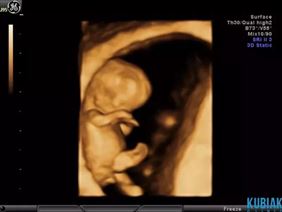

Kobietom w ciąży zapewniamy opiekę przez cały okres jej trwania. W tym celu przeprowadzamy badania ultrasonograficzne, podczas których sprawdzamy, jak rozwija się płód i oceniamy płyn owodniowy oraz łożysko. Kontrolujemy również przepływy naczyniowe u płodu i matki, wykorzystując do tego aparaturę dopplerowską.